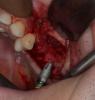

CSS Опубликовано 26 декабря, 2012 Поделиться Опубликовано 26 декабря, 2012 Уважаемые коллеги, очередной экспериментальный синус с использованием аллогенов!!! Ждемс результатов!!!P.S. И естественно жду Ваших коммментов и замечаний!!! ;-))) 4 Ссылка на комментарий

CSS Опубликовано 26 декабря, 2012 Автор Поделиться Опубликовано 26 декабря, 2012 спасибо, хорошие фотки. А почему эксперимент?Такое впечатление по ОПТГ после синусов, что в 1 сегменте графт пополз скврзь мембрану, как бы нет уровня имхоСпасибо за кейс.Эксперимент с Алло, это немецкий материал, смесь кортикальной и губчатой кости. Использовал впервые. Относительно проползания графта, там очень сложная анатомия была, за 3 мес до этого было удаление с перфами. Слизистая утолщена, и отслоена целой. Рентген - это доп метод!!! ;-))) Под слизистой Prp и Алло мембрана из фасции!!! Ссылка на комментарий

CSS Опубликовано 26 декабря, 2012 Автор Поделиться Опубликовано 26 декабря, 2012 чем отслаивали окно в синус от мембраны?какой алло материал использовали? И пропилы и отслойка, пьезо, далее кюретами. Тут Даск. Про Алло, материал Остеографт, пока не зарегиный в РФ, смесь кортикалки и губки!!! Производят немцы. Ассортимент масштабный, есть и комбинирированные гиалуронкой и деминерализированные, но я хочу сам разобраться, что лучше и интереснее для меня. Цена реально смешная, по сравнению с синтетиками и ксенографтами. Ждемс результатов. Через 4 мес контр КТ и решим, что там выросло, а то мож на эндоскопическую санацию синуса прийдется пацика посылать!!!! ;-)))))) Ссылка на комментарий